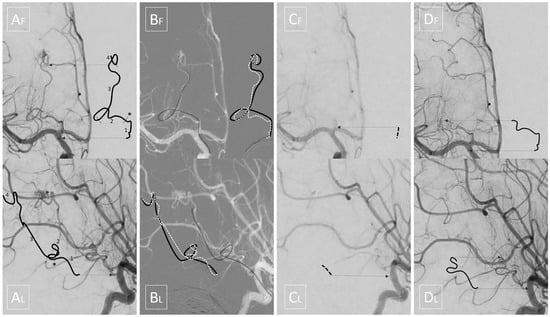

A preoperative three vessel angiography (bilateral internal carotid artery and dominant vertebral artery) confirmed the presence of a slightly enlarged right anterior choroidal artery feeding the tumoral blush. No feeders were observed from the posterior circulation; embolization was obtained with n-butyl cyanoacrylate (NBCA) superselective injection (0.4 mL) via a microcatheter (Magic 1.2F-Balt, Montmorency, France; aided by a microguidewire Hybrid 0.008-Balt, Montmorency, France) navigated near the tumor pedicle, distally, to the plexal point of the anterior choroidal artery (Figure 2). The positioning of the microcatheter distally, in the anterior choroidal artery, determined, as expected, a rectification of the artery, and a panoramic injection (guiding catheter Envoy 5F-Codman Neuro, Raynham, MA-positioned in the internal carotid artery) revealed an absence of flow within the anterior choroidal artery. The total time that elapsed between micro-catheterization, glue injection and retrieval of the microcatheter was 6 min. The subsequent control angiography revealed the exclusion of the tumor blush and a re-opening of the anterior choroidal artery. Total contrast media of 30 mL (300 mgI/mL), fluoroscopy time was 11 min, total series of 9, and cumulative DAP 20 710 mGycm2.

Immediately after the endovascular procedure, the patient underwent a surgical excision of the tumor. Opening of the right parietal craniotomy and dura revealed a herniation of the superior parietal lobule. The cortex was incised, leading to the spontaneous drainage of an intralesional haemorrhage and the identification of the neoplastic tissue, which was soft and scarcely bleeding. A gross total resection was easily achieved and an external drainage was left for 4 days postoperatively and then removed. Total blood loss was estimated to be approximately 200 cc, mainly during soft tissue opening. Histopathological analysis of the specimen was consistent with WHO grade III choroid plexus carcinoma (Immunophenotype S100: +; CAM 5-2: +; MNF116: +, MIB1 > 20%). The patient was discharged at 8 days with no neurological sequelae, and was planned for adjuvant chemotherapy according to CPT-SIOP 2009 recommendation (6 cycles alternating Cyclophosphamide and Carboplatin). Follow-up at 3 months revealed regular development of the child and absence of recurrent disease at MRI (Figure 3).

As mentioned above, we highlight a source of potential complication, which is insidious due to the specific pathology and populations affected. Indeed, it is otherwise infrequent for neurointerventional radiologists to navigate long segments of an eloquent artery that is only mildly enlarged by the underlying pathology (contrary to AVMs). Moreover, since contrast and dose sparing are required for pediatric interventions, it is also advisable to perform only strictly necessary control angiograms. Therefore, a potential absence of flow can be easily overlooked. Our case clearly demonstrates that the rectification of the artery, even using the smallest microcatheters and in the absence of spasm, may be sufficient to completely stop the flow along the whole course of the anterior choroidal artery, even proximally to the plexal point, where eloquent perforators are located (Figure 4). It is our opinion that the time from entrance to exit in the anterior choroidal artery should be monitored and regarded as a potential ‘occlusion time’ in this specific subset of patients. In fact, it may explain some of the complications reported in recent literature and it should be minimized, not only by the expertise, but also by the choice of fast embolic agents.

Figure 4. Upper quadrants display frontal views while lower quadrants display corresponding lateral views. Shifted lines are intended, as in Figure 1, to help the reader in localizing the intended segments. (A) Initial angiography: segment 1 is the cisternal portion of the anterior choroidal artery; the asterisk * corresponds to the plexal point that marks the entrance in the ventricle; segment 2 is the intraventricular segment which, in this case, is tortuous and ventrally dislocated by the tumor; segment 3 is the tumoral segment of the artery running along the surface of the tumor; segment 4 is the tumoral pedicle which penetrates the mass giving rise to the tumoral blush. (B) The black solid line depicts the arterial course stretched by the microcatheter, while the white dashed line depicts its anatomical course. (C) Panoramic angiography with the microcatheter inside the anterior choroidal artery; note that no flow is seen in the distal part of the cisternal segment of the anterior choroidal artery, and even the proximal part is barely visible. (D) Final angiography shows flow restored to the cisternal and intraventricular segments.